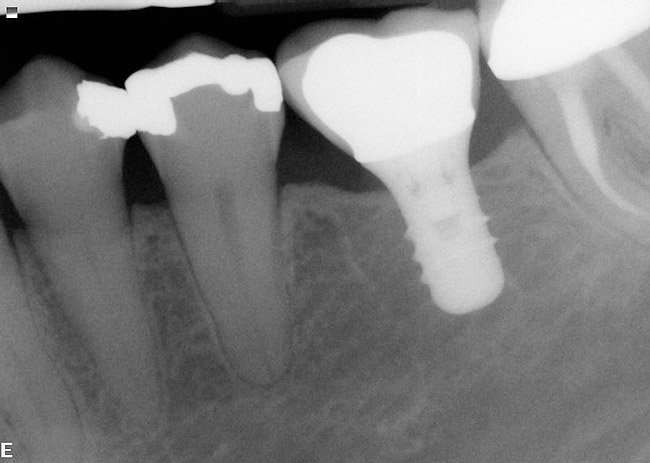

Figure 7  Following removal of a mandibular first molar an osteotomy was performed in the interradicular bone, a guide pin placed, and a radiograph taken.

Figure 7

Figure 8  A straight-walled implant with a 4.8-mm diameter and a 6.5-mm restorative platform diameter has been placed in the interradicular bone following tooth sectioning and removal. Primary stability has been attained.

Figure 8

Figure 9: Following manipulation of the interradicular bone, implant placement, and performance of concomitant regenerative therapy, the hard tissues are mature and the implant is ready for restoration.

Figure 9

Figure 10  A radiograph taken 54 months after implant restoration demonstrates the stability of the crestal peri-implant bone.

Figure 10

If the most crestal aspect of the interradicular bone is at least 3-mm-wide mesio-distally: A 2.2-mm-wide guide bur is drilled to the appropriate length, a guide pin is inserted, and a radiograph is taken (Figure 7). If necessary, the initial osteotomy is extended apically. A tapered osteotome is inserted into the osteotomy and moved mesio-distally and bucco-lingually to expand the osteotomy site. A 2.8-mm bur is used to prepare the osteotomy to depth, and a 2.8-mm-wide tapered osteotome is inserted in the osteotomy and once again utilized in mesio-distal and bucco-lingual directions to expand the osteotomy site. If the mesial and distal aspects of the interradicular bone are still intact at this point, a 3.5-mm bur is utilized to prepare the osteotomy to depth. A 3.5-mm-wide osteotome is inserted into the osteotomy and utilized in the manner already described. A decision is made as to whether to place a tapered implant with a 4.1-mm-wide base and a 6.5-mm-wide neck, or to use a 4.8-mm-wide bur and prepare the osteotomy to depth, in anticipation of placement of an implant with a 4.8-mm-wide parallel wall body and a 6.5-mm-wide platform. The chosen implant is inserted into the osteotomy (Figure 8), appropriate regenerative materials are placed, and the flaps are sutured. Following maturation of the regenerating hard tissues, the implant is ready for restoration (Figure 9). A radiograph taken 54 months after implant restoration demonstrates stability of the peri-implant crestal bone (Figure 10).